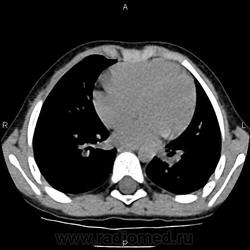

Туморозный бронхоаденит?

Ребенок 4 лет: жалоб -нет, объективно - без особенностей, ДСТ - 20 мм. Подскажите, пожалуйста, коллеги, как расценить картину в левом корне. (туберкулез ВГЛУ  в фазе обызвествления? )

с активным туберкулезом ВГЛУ в фазе инфильтрации и частичного обызвествления. Ребенок болеет давно. Откуда он?  Из ближнего зарубежья или наш Российский. Интерсно знать.

Ребенок наш. Ранее у фтизиатров не наблюдался. Туберкулезный контакт - IV "А" гр. 1.5 мес назад -  РМ - 11мм.